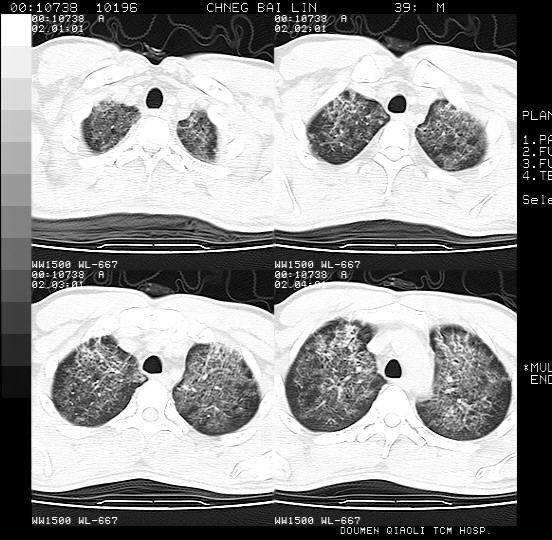

男,39岁。10天前自觉感冒,曾输液一次内容不详曾有吸毒史。现有咳嗽、咳痰胸闷。

双肺弥漫性网状、磨玻璃样病灶,边界不清。有吸毒史。首先考虑机遇性肺部感染。

两肺弥漫间质改变,考虑1、特发性肺间质纤维化。2、间质性肺炎。

双肺野蜂窝状结构及多发斑片状影,高度怀疑卡氏囊虫性肺炎

两肺弥漫分布的网状毛玻璃状阴影,边缘模糊不清,纵隔未见明显淋巴结肿大

诊断:机遇性肺部感染

鉴别诊断:1特发性肺纤维化,主要部位在两肺下叶胸膜下网状,毛玻璃状及蜂窝状阴影,临近胸膜增厚,该病征象不太符合